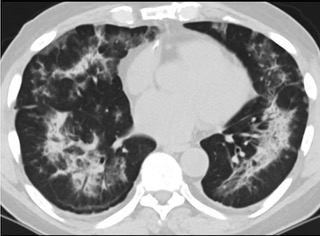

疑點(diǎn)二,中國(guó)科研工作者從60篇研究論文中篩選出142位電子煙肺炎患者的250張影像圖片,邀請(qǐng)3位放射科權(quán)威專家,對(duì)上述全部影像圖片、相關(guān)病人臨床信息以及文獻(xiàn)原文進(jìn)行了仔細(xì)全面研究與審查,又有了新的發(fā)現(xiàn)。

6天后的軸向CT平掃圖像顯示毛玻璃影變?yōu)閷?shí)變和輕度結(jié)構(gòu)扭曲。(同一病人CT影像)

16位被文獻(xiàn)報(bào)道為電子煙肺炎的患者被專家判定為“病毒性感染”,即有可能是新冠肺炎的“疑診患者”,其中更有5位臨床癥狀和治療情況相對(duì)完整的患者被判定為“中度可疑”。因此在2019年美國(guó)報(bào)道的電子煙肺炎中存在病毒性感染的病例,而且不排除美國(guó)電子煙肺炎中存在新冠肺炎的可能性。